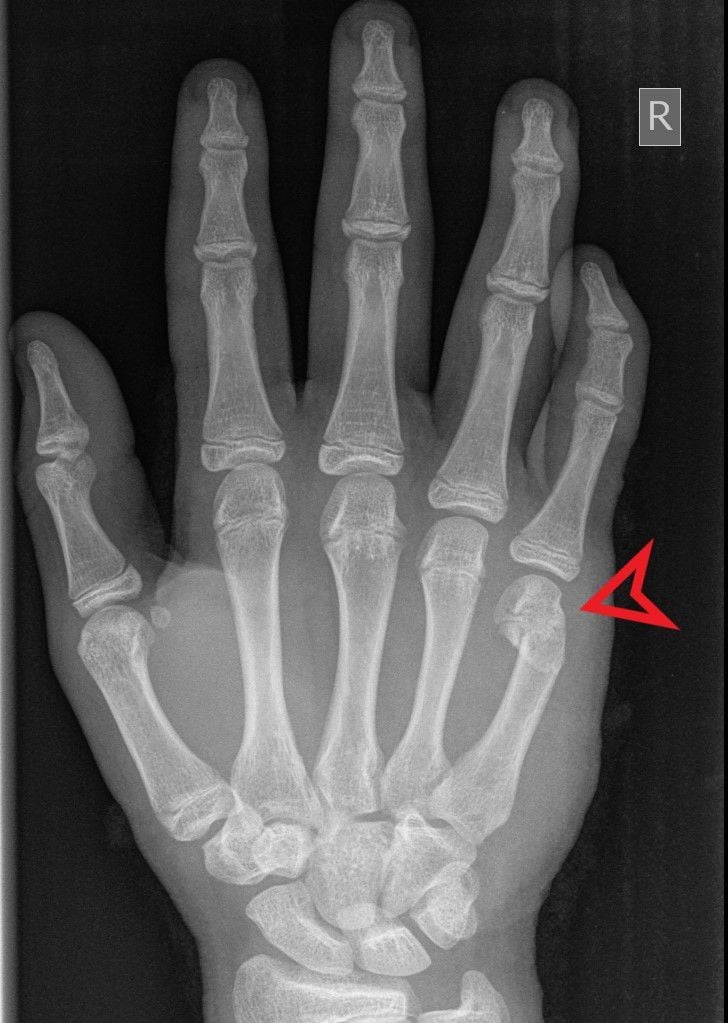

boks esnasında çoğunlukla yumruğunu gevşek tutması sonucu oluşan kırıktır.

4. ve 5. metakarp ( son iki parmak) boyun kırığıdır.

anın sıcaklığı ile hissedilmeyen fakat sonrasında şişerek kendini belli eden acemi işi kırıktır.

kendi kemiğini kıran yumruk vurduğu yeri ne hale getirir diye düşünen varsa düşünmesin, ortalama iki aylık tatlış bir alçı süreci, sonrasındaki fizik tedavi ve falan filan her şeyi unutturur.